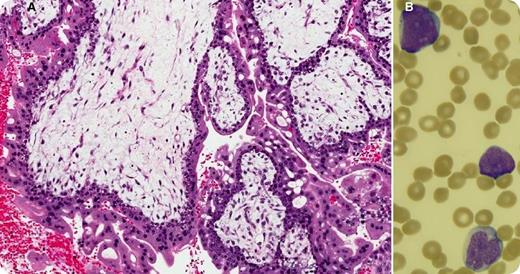

Thirteen months after the successful treatment of a persistent complete hydatidiform mole (panel A: diffusely hydropic, grape-like chorionic villi surrounded by hyperplastic atypical trophoblast), a 27-year-old woman with no family history of cancer presented with fatigue, sore throat, and petechiae for a few weeks. Her prior treatment included a single cycle of single-agent methotrexate that was followed, because of a further increase in human chorionic gonadotropin, by 9 biweekly cycles of etoposide, methotrexate, dactinomycin, cyclophosphamide, and vincristine (EMA/CO regimen). Blood work at this time showed hemoglobin, 10.9 g/dL; white blood cells, 41.4 × 109/L; platelets, 15 × 109/L; and 60% blasts (panel B). The bone marrow was packed (95% cellularity) with immature myeloid cells that stained positively for CD13, CD33, CD34, and myeloperoxidase and negatively for CD3. Cytogenetic analysis revealed a core-binding factor β rearrangement at 16q22. A diagnosis of therapy-related acute myeloid leukemia (t-AML) was established.

Although t-AML after exposure to alkylating agents has a latency of 5 to 7 years, t-AML after exposure to topoisomerase II (TopoII) inhibitors has a shorter latency (1-3 years). Containing 2 TopoII inhibitors, 1 alkylating agent, 1 antitubilin agent, and 1 antimetabolite, EMA/CO carries a high risk of about 0.7% for future t-AML, and patients need close follow-up for several years after treatment.